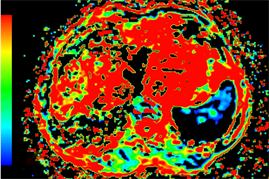

Figure 2. Axial MRI images of the same patient as in Figure 1 after TACE treatment. (a) T1-weighted unenhanced image shows a hypointensive lesion in right lobe of liver. (b) Arterial phase contrast-enhanced image shows the central necrotic area and peripheral enhanced area in the lesion. (c) ADC map. (d) Dslow map. (e) Dfast map. (f) f map.